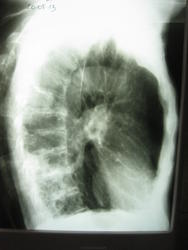

Левое легкое явно отличается по прозрачности от правого: и межреберные промежутки, и обеднение легочного рисунка. Боковой снимок - правый или левый?неясно.

Сделать бы Р-гр. левый бок и прямой снимок с захватом н\отд.

Это левый боковой снимок ) Еще и неправильно подписан (

А попробовать ещё можно линейную томографию,коли нет компьютерной.Взять надо ниже представленных томограмм и срезы начать бы с 6см.

ТМГ бы сделал на левый корень!!!